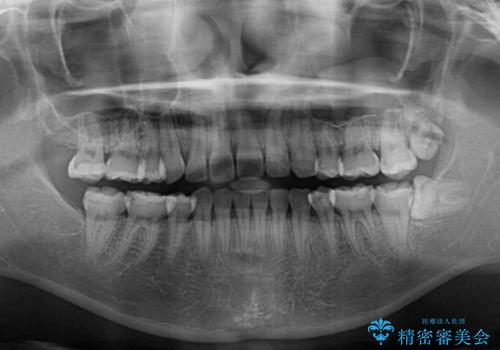

- 八重歯やデコボコをインビザラインで治療したいとのことで来院された患者様です。

インビザライン単体で治療を行うには叢生が強いと判断されたため、事前にワイヤー装置で抜歯矯正を行い、ある程度改善してからインビザラインにて仕上げていくこととしました。